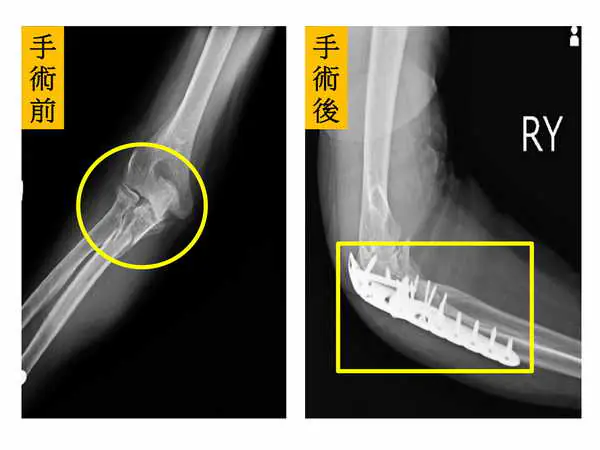

圖二:【左圖】術前X光片顯示病人手肘呈現粉碎性骨折(圓圈處);【右圖】術後病人手肘關節已活動自如,生活恢復正常(方框處)。